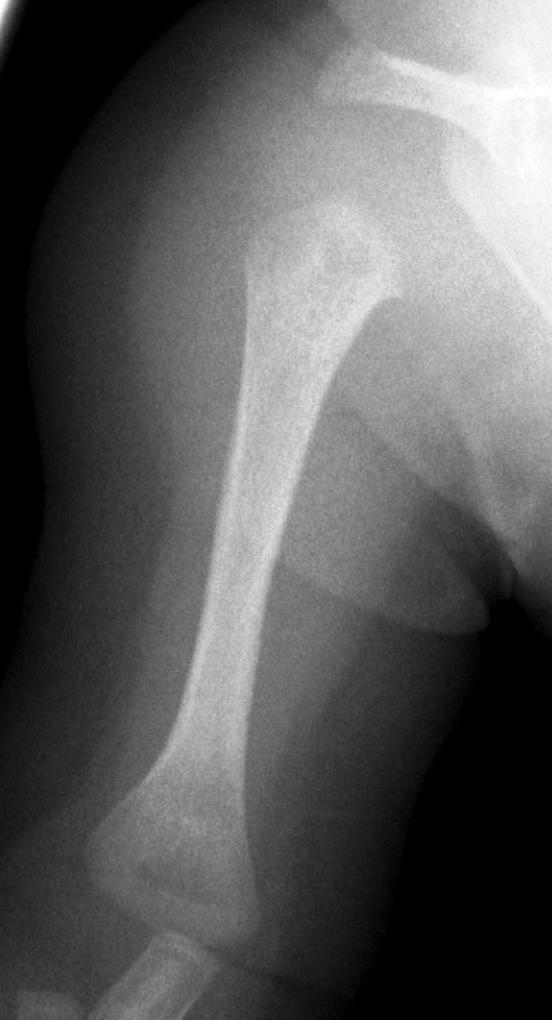

37. a-d) X-ray of the right humerus. a. Rarefaction in the proximal-medial part of metaphysis of the right humerus – early osteomyelitis. b. Two weeks after the lytic area has grown. c. 1 month later sclerotic regeneration has begun. d. 4 months after almost complete healing. Osteomyelitis, infant.